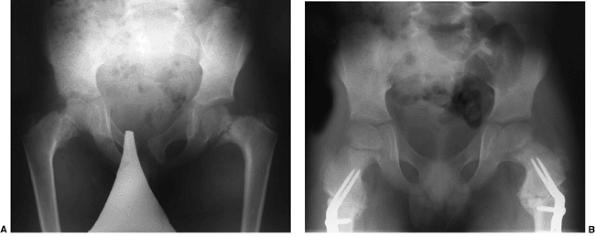

![]() |

Figure 27.17 Patient with cloacal exstrophy.A: Clinical photo. B: Radiograph before closure. C: Radiograph 2 months after closure. D: Radiograph 6 years after closure. (Courtesy of Paul Sponseller.)